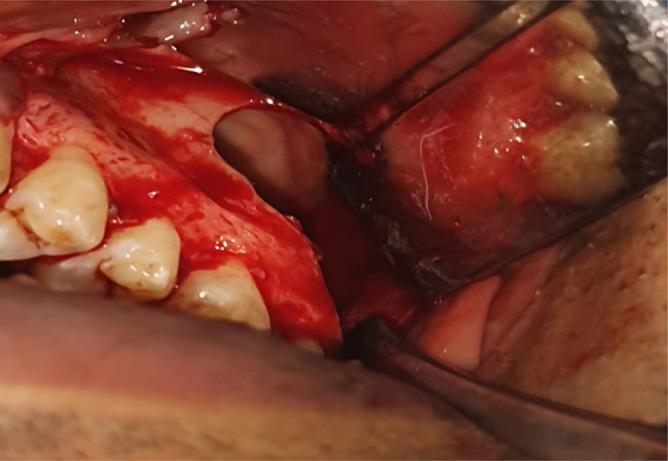

Odontogenic keratocyst is a benign intraosseous lesion of odontogenic origin which is characterized by its aggressive nature. It is usually present in the mandibular posterior area, although it can also be found in the maxilla, particularly in the canine region. We discuss a unique example of OKC in the maxillary sinus involving the 27&28 region. Due to comparable clinical signs, this lesion is more prone to be mistaken for other lesions of the maxillary sinus, such as sinusitis or polyps. On the other side, this benign disease has the potential to develop into Ameloblastoma or squamous cell carcinoma. A favorable prognosis thus depends on early identification, precise diagnosis, appropriate treatment, and follow-ups.